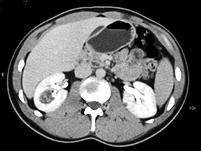

问题 男,45岁,右腰部隐痛不适伴无痛性肉眼血尿1个月,请结合图像,选择最可能诊断 ( )

选项 A、右肾盂癌 B、右肾脓肿 C、右肾血管平滑肌脂肪瘤 D、右肾感染性囊肿 E、右肾癌

答案 E